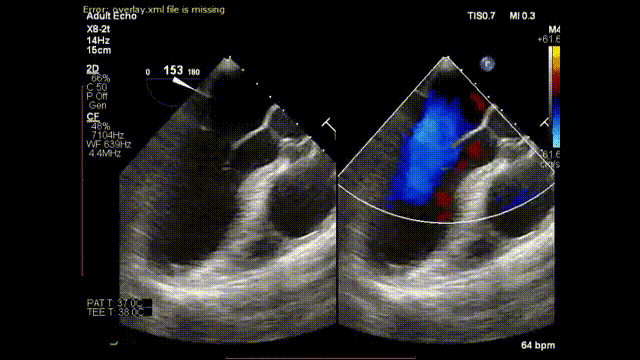

患者吴先生,52岁,患二尖瓣关闭不全10多年,术前超声诊断:二尖瓣后叶脱垂、伴重度反流、左房增大。经中山医院王春生教授、魏来教授团队综合评估分析,决定使用北京迈迪顶峰医疗科技股份有限公司研发的“E-ChordTM二尖瓣修复装置”进行腱索重建手术。

术前反流情况